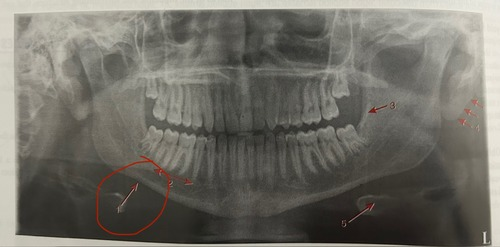

Lingual foramen surrounded by genial tubercles

External oblique ridge

Mental foramen

Mental fossa

Mental ridge (premolar & incisor region)

Inferior border of mandible